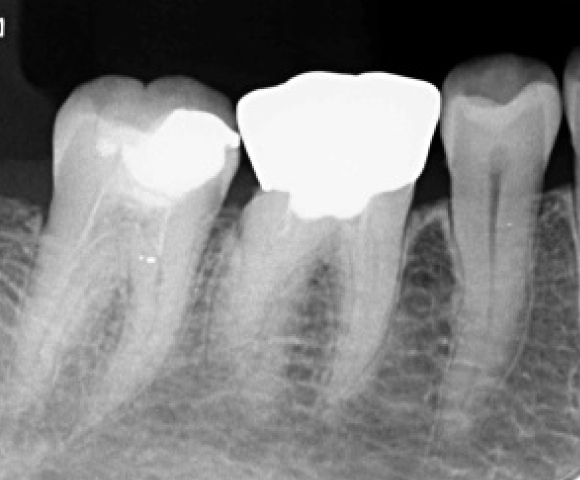

エックス線検査

根の中の治療もしっかりしていきます

歯周病治療後被せ物をしっかりフィットさせることで歯周病の再発を防ぎます。

治療前(症例)

治療後(症例)

治療前、被せ物と冠の間に段差がありフィットしていませんが、歯周病治療後しっかりと被せ物をフィットできています。